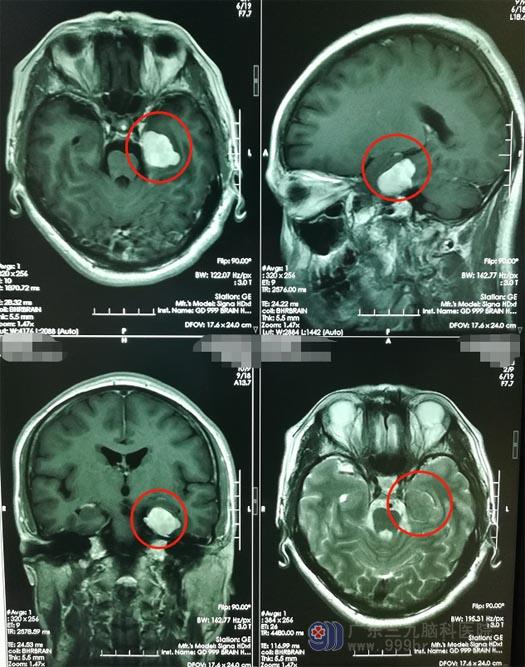

一个月前,李大姐在凌晨突然出现意识障碍,呼喊不应,伴有左侧嘴角流涎,持续约10分钟后清醒,醒后不能回忆发作过程,当地医院查头颅MR提示“左侧海马病变”。

心急如焚的家人来到了广东三九脑科医院神经外五科。进一步头颅MR检查显示:左侧颞部内侧-小脑幕上占位性病变,考虑脑膜瘤可能性大。